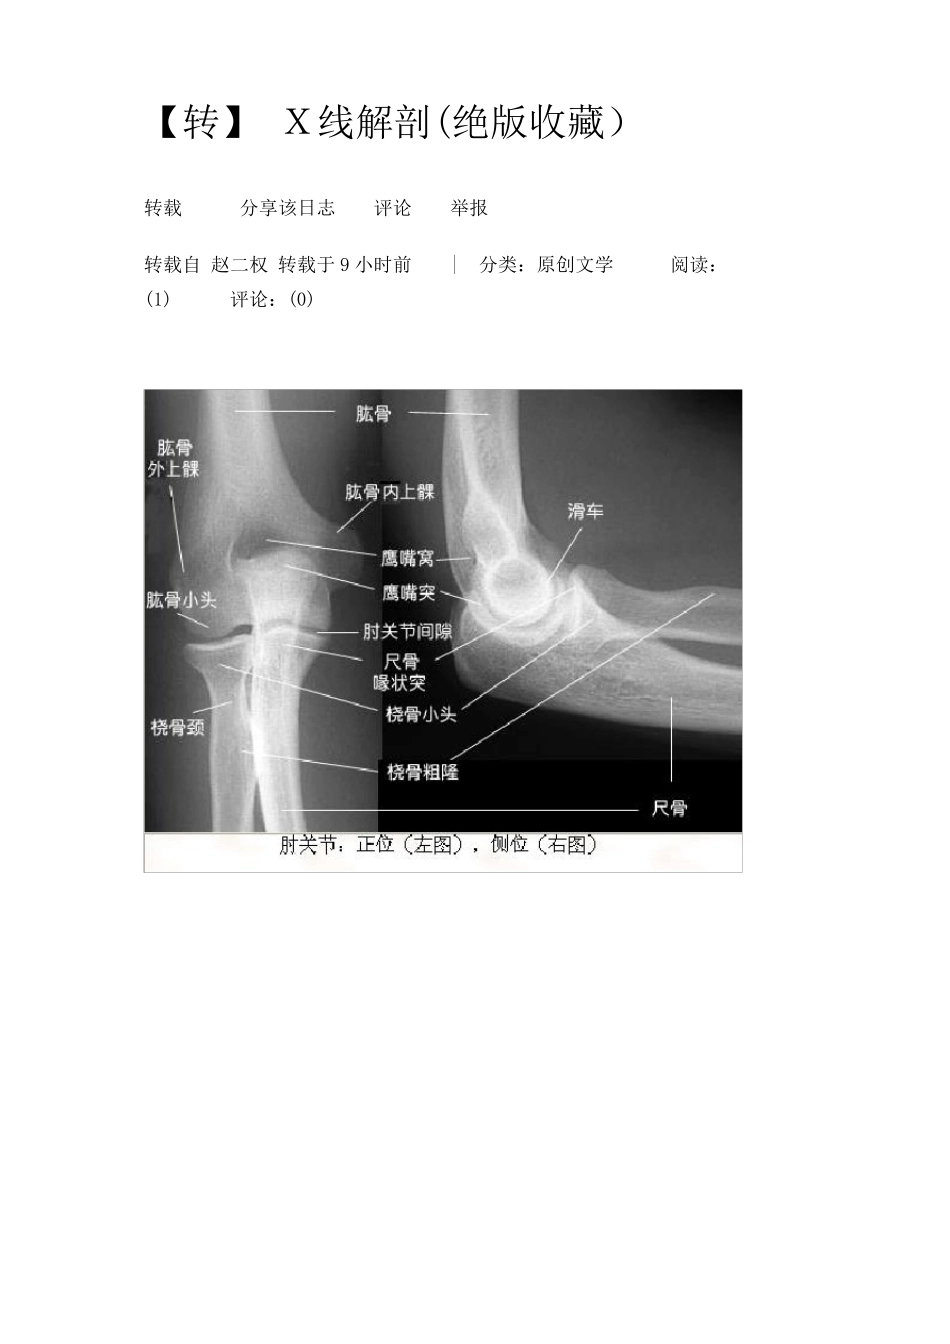

【转】 X线解剖(绝版收藏) 转载 分享该日志 评论 举报 转载自 赵二权 转载于 9 小时前 | 分类:原创文学 阅读:(1) 评论:(0) 胸部X 线片系统读片原理 24 个字母(A-X)系统读片法,可以减少漏诊。 胸部X 线片系统读片原理 A(Airway)气道在胸上部,看它是否居中,脊柱是否直线经过,气管有无移位,有无纤维组织牵拉使肺容积缩牵、过度充气及压迫。有无支气管气管巨大症,肺叶开口压迫、狭窄、隆突受压等支气管肺癌征象。 B(Bone)肋骨距是否某侧缩窄,肋骨有无缺损,如第一肋骨上缘缺损,有硬皮病、类风湿性关节炎的可能。第 7~9 肋骨下缘缺损示主动脉狭窄,见于儿童先天心脏病;法乐氏四联症可见左肋下缘缺损。咳嗽所致骨折,可见于 6~9 肋,第 7肋腋后线可见叉形肋。鸽胸与先天性房室间隔缺损相关,也见于儿童哮喘症或脊柱侧凸严重时伴通气功能降低者。骨脱钙可见于类固醇治疗患者、老年、肾病、或其他代 谢 病者。 C(Cor)心脏右 缘有两 弓 ,左缘有四弓 。右 两 弓 消 失 见于漏斗 胸、右 中叶萎 缩、肺炎。形状 变 化 或心脏扩 大,见于先天性心脏病、心力 衰 竭 。 D(Diaphragm)膈肌右高于左半个肋间隙,一侧高,考虑胸部肿瘤、纤维组织牵拉、膈下脓肿。半侧膈肌升高考虑外伤、中风、颈部感染或肿瘤、肺炎或放射治疗后。右侧可见膈肌伴弯刀征。医 学.教育 网原 。创 E(Esophagus)食管位于气管右,若有空气液面,考虑食管不能松驰或狭窄。 F(Fissures)肺裂将各肺分为各叶,左右各有一斜裂,右侧有横裂,斜裂下端止于膈肌,决不止于前胸壁,有异常时示有病变。 G(Gastric bubble )胃泡在左侧,若在右,考虑内脏转位,胃泡不见,考虑食管不能松驰。胃泡在心右可能为膈疝。 H(Hila)肺门移位示肺部分萎缩、过度充气等,肺门区扩大可能是肺癌转移、肺内感染、免疫疾病或结节病。 I(Interstitium)间质性浸润分两型,间质型看上部心前区,下部可因妇妇女乳房影加重。肺泡型浸润,因肺泡灌注水、脓、血或蛋白质样物质,见于Goodpasture 氏征、肺含铁血黄素沉着症、鳞状上皮脱落间质性肺炎等。观察咳出 物对 鉴 别 诊 断 有用 。医学 教。育网 原.创 J(Junction lines)连 接 线 是垂 直 的 ,仅 见于纵 膈,有右脊 柱 旁 、右主 动 脉 旁 、右心旁 线 ,左脊 柱 旁 、左主 动 脉 旁 、左心旁 线 ,前后连 接 线 等,一般 看...